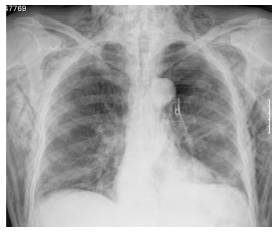

Na auscultação pulmonar verificava-se uma diminuição dos sons respiratórios no hemitórax esquerdo e sibilos de predomínio expiratório no hemitórax direito. A telerradiografia torácica (Fig. 1-A) confirmou a presença de pneumotórax à esquerda, tendo sido efectuada drenagem torácica (dreno de Joly n.º18, na linha medioclavicular à esquerda). Apesar do correcto posicionamento do dreno (funcionante e a borbulhar com os movimentos respiratórios), verificou-se uma expansão apenas parcial do pulmão esquerdo (Fig. 1-B).

Fig. 1 Telerradiografia torácica na admissão (A) e após colocação do dreno torácico (B)